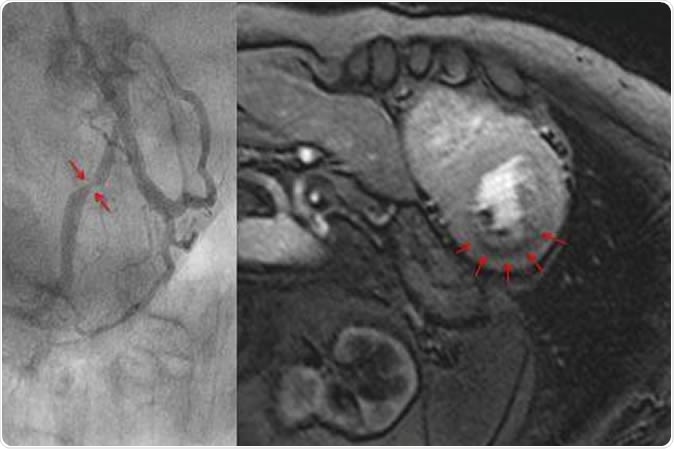

Measuring blood flow in the myocardium with magnet resonance imaging (top). The dark area in the myocardium (arrows) shows a pronounced reduction of blood flow. The cardiac catheterization of the same patient (bottom) shows a clear constriction of the artery. Image Credit: Eike Nagel, Goethe University